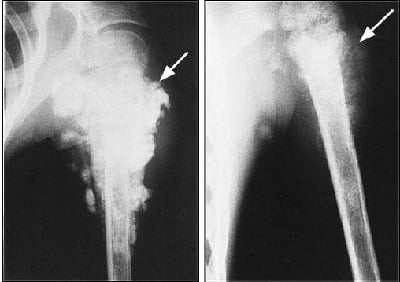

Из-за схожести признаков опухоли с воспалительными процессами, в некоторых случаях производится неправильная диагностика, а, следовательно, и лечение назначается ошибочное. Диагностика остеосаркомы опирается на рентгенологические данные в совокупности с гистопатологическими критериями.

- Рентгенологическое исследование. Дает крайне разнообразное представление о месторасположении и развитии опухоли. Показывает изменения костей и их элементов. Характерный признак, по которому в процессе рентгенологического исследования можно судить о развитии остеосаркомы — «треугольник Кодмена». Это своеобразная треугольная шпора или «козырек». К ним можно добавить и игольчатые спикулы, также свидетельствующие о развитии патологии.